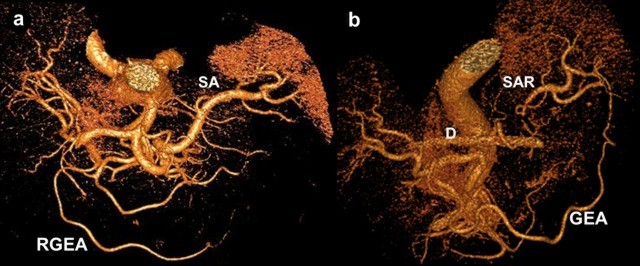

Preceding surgery, the splenic artery was always seen on CT angiography as a thick stem with no other branches travelling to the spleen (Figures 7a and 8a). As a consequence of splenic artery resection, the whole or the bulk of its trunk were no longer available for evaluation by CT angiography after a spleen-preserving distal pancreatectomy with resection of the splenic vessels and, in all 10 cases, the gastroepiploic arcade was seen to have become the “highway” to the spleen within 7-30 days after surgery (Figures 7b, 8b, and 9). In two cases, due to technical reasons, 3D CT angiography was only carried out postoperatively but, in both cases, there were no doubts about the source of the blood supply to the spleen (Figure 9). In none of the 10 cases was any appreciable blood flow through the short gastric arteries visualized.

Figure 7. Celiaco-mesenterial anatomy in а 53-year-old man with chronic pancreatitis of the distal type. 3D CT angiography after the renal artery images were eliminated. Vertical view. a. Before surgery: the splenic artery thick trunk with no collaterals is shown. b. Fourteen days after a spleen-sparing distal pancreatectomy with resection of the splenic vessels: the spleen is fed through the gastroepiploic arcade. There are no other detectable major arteries to feed the spleen. D: drainage tube; GEA: gastroepiploic arcade; RGEA: right gastroepiploic artery; SA splenic artery; SAR: splenic artery remnant |